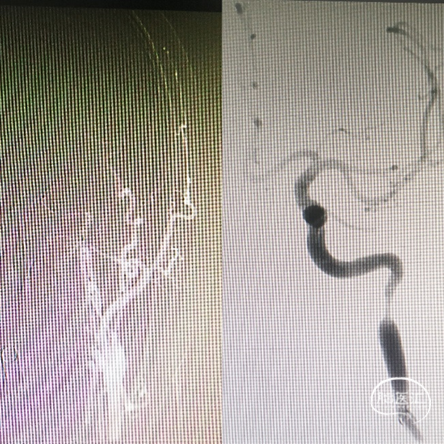

在球囊支撑下将6F NeuronMax越过C1段狭窄,回收保护伞,造影发现MCA上干闭塞。

微导丝、微导管引导下将ACE60抽吸导管超选到上干闭塞处,负压泵持续抽吸。

血管再通后,保护伞下,5mm×30mm球囊扩张后,颈内动脉C1段狭窄处置入9×40mm支架。